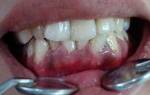

На фотографии изображен кариес в пришеечной части зубов.

Распространение кариеса чаще всего происходит между зубами, в фиссурах (бороздки и канавки) зубов, в пришеечной части зубов. Для того чтобы его обнаружить стоматологи используют различные методы обследования.

На фотографии кариес, который образовался между зубами.